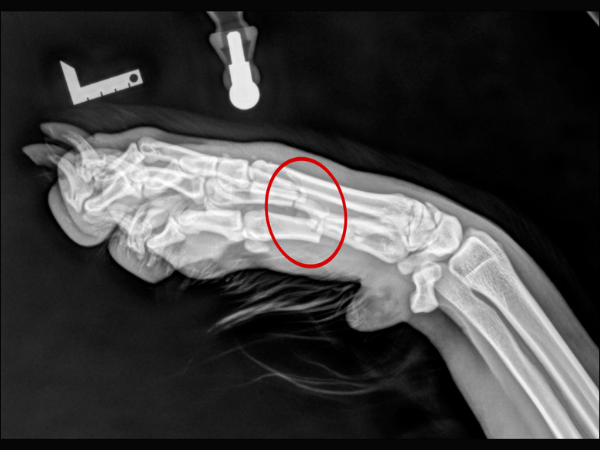

<術前のレントゲン>

第2・3・4指中手骨を骨折しています。

▼術前